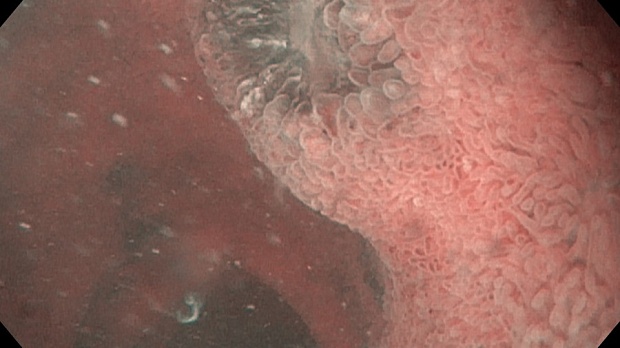

меланома ДПК.jpeg)

меланома ДПК.jpeg)

меланома ДПК.jpeg)

меланома ДПК.jpeg)

Эзофагогастродуоденоскопия диагностическая

12-кишка: Просвет луковицы двенадцатиперстной кишки обычный, содержит небольшое количество желчи, перистальтика активная , слизистая оболочка розового цвета, ворсинки сохранены. Так же прослеживаются пигментированные образования от 2мм до 8мм. серо-синюшного оттенка. Постбульбарном отделе множественные пигментые образования до 10мм, единичные кратообразные пигментные образования до 15мм, глубиной до 5мм., дно покрыто серым фибрином. Биопсия 2-а кусочка.

Заключение: ГПОД. Грыжевая гастропатия. Эрозивная гастропатия антрального отдела желудка. MTS Меланома ЛДПК, залуковичного отдела. Биопсия.